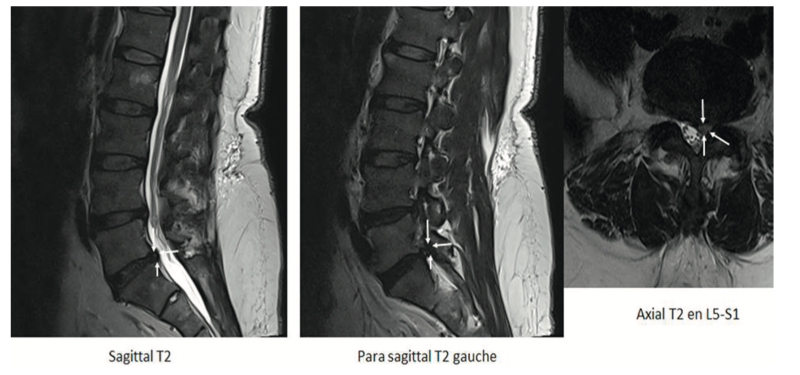

Fig. 7.8.

Hernie postéro-latérale gauche L5-S1 en hypersignal modéré (potentiellement exclue), conflictuelle avec l'émergence durale de la racine S1 gauche (flèches blanches).

(Source : création de l'auteur)